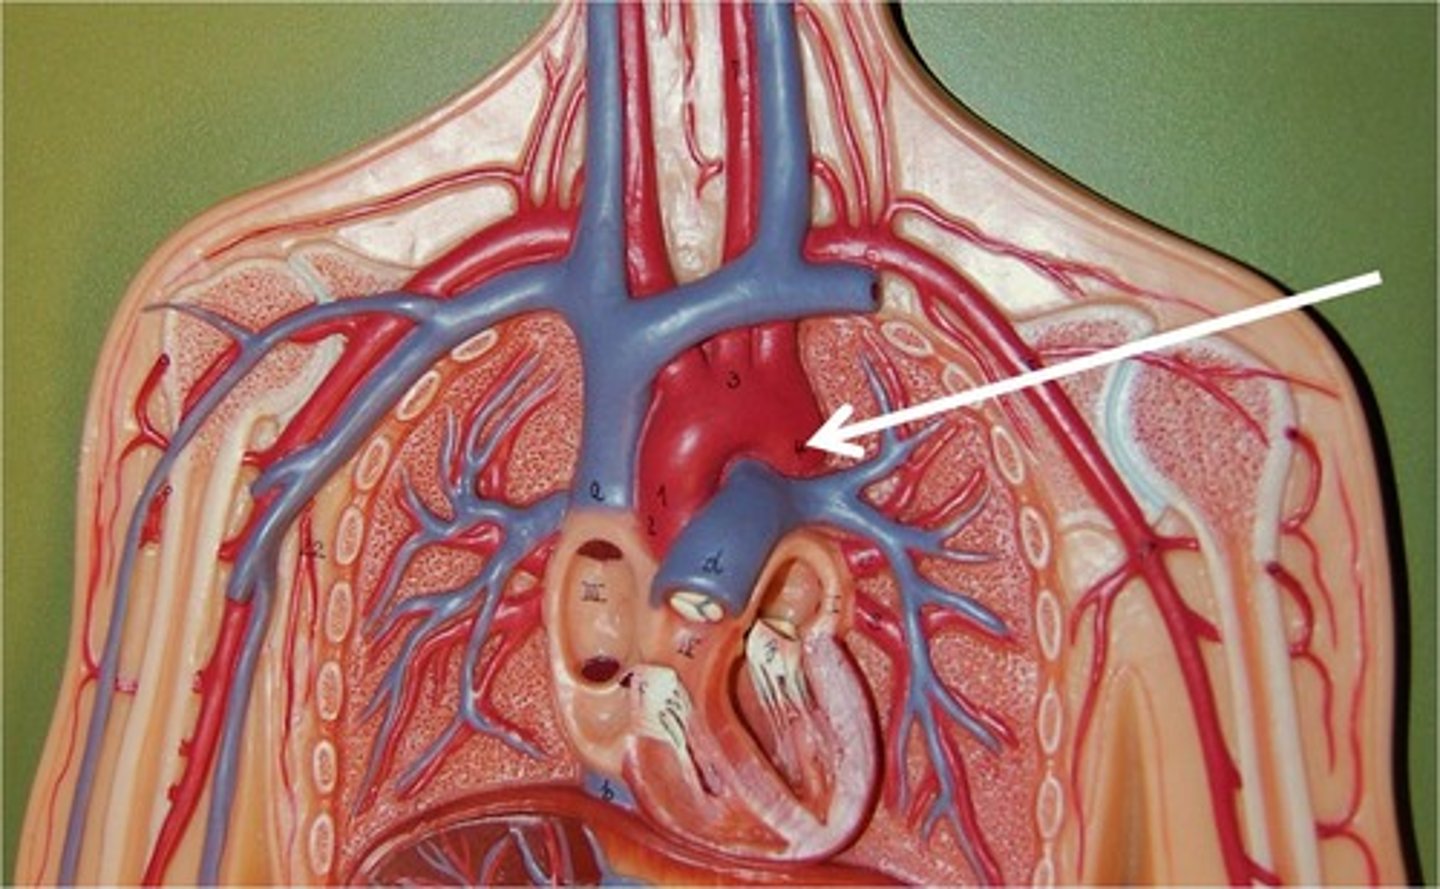

brachiocephalic vein

subclavian vein

superior vena cava

axillary vein